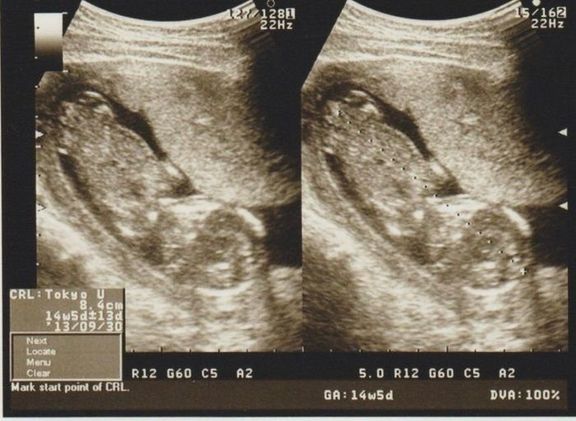

命の始まりは神秘的!2D・3D・4Dのエコー写真で見る「私と赤ちゃんの実録260日」 -

直前でまさかの性転換?みんなの予想を裏切り、ある日突然男の子になった我が子 -

エコー写真とともに綴る、愛しい我が子との“絆”を実感した妊娠期~ママと娘の265日~ -

エコー写真とともに綴る、愛しい我が子との“絆”を実感した妊娠期~ママと娘の265日~ -

緊急帝王切開で誕生。エコー写真で綴る息子と過ごした252日 -

緊急帝王切開で誕生。エコー写真で綴る息子と過ごした252日 -

不妊治療や2度の流産経験を経て「初めての出産」。日々成長する胎児の記録をエコー画像で振り返る -

待望の妊娠判明!エコー写真に見る、我が子を胸に抱くまでの“命の軌跡275日” -

エコー画像で振り返る、私に宿った小さな命が大きく育って誕生するまでの記録 -

推定体重は3773g!骨盤に入らず緊急帝王切開になった長女の成長をエコー写真で振り返る -

生まれる前からエコーを通して対面し、長女を少しずつお姉ちゃんにしてくれた次女の存在 -

生まれる前からエコーを通して対面し、長女を少しずつお姉ちゃんにしてくれた次女の存在